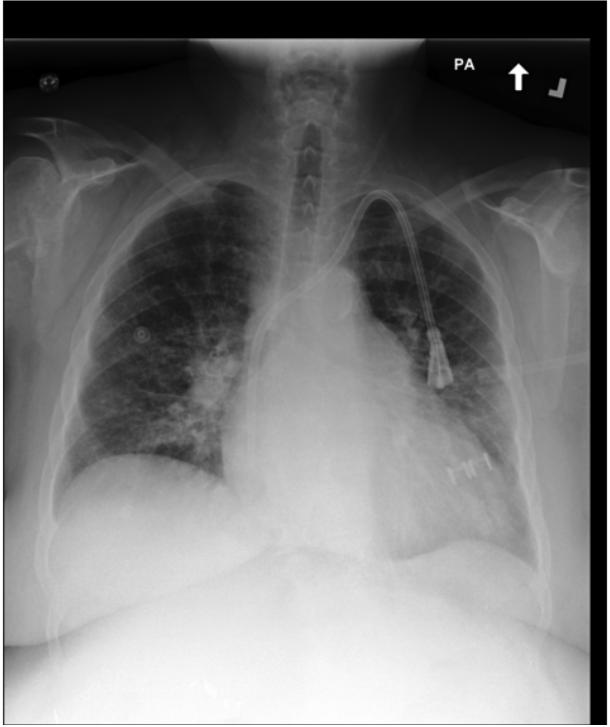

Datasets. CURE adopts a multi-task fine-tuning strategy on the same three publicly available chest X-ray datasets used by our baseline (MAIRA-2), enabling a fair and comparable evaluation. Chest ImaGenome [53] provides scene graphs linking anatomical regions to bounding boxes and report sentences, and is used for the Anatomy-Grounded Report Generation task. PadChest-GR [11] contains radiology reports with phrases explicitly grounded to bounding boxes, supporting both Grounded Report Generation and Phrase Grounding tasks. MS-CXR [5] is a smaller dataset derived from MIMIC-CXR [17], providing bounding box annotations for report phrases, and is used exclusively for Phrase Grounding. For zero-shot evaluation, we also include VinDr-CXR [32], using its official test split to assess the model’s generalization to unseen data distributions.

To assess model robustness against domain shifts and unseen data distributions, we employ the VinDr-CXR dataset [32] as a zero-shot benchmark.

Dataset Characteristics.

VinDr-CXR consists of 15,000 training and 3000 testing frontal-view Chest X-rays. Each image was annotated by a consensus of three radiologists for the presence of 28 common thoracic diseases and findings. These findings are categorized into 22 localizable classes (annotated with bounding boxes) and 6 global classes (image-level labels only).